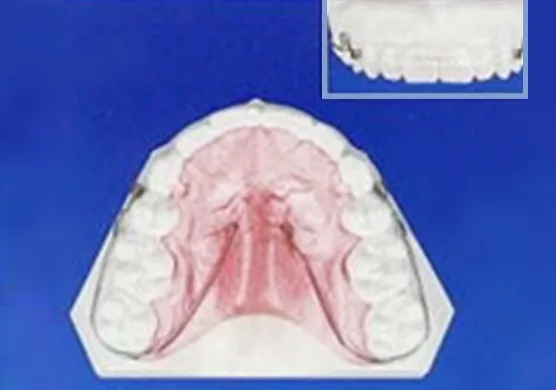

矯正治療終了後の装置

保定装置(リテーナー)

歯がきれいに並んでも、装置を外すと歯が後戻りする場合があるため、装置の除去後に保定装置を装着します。数ヵ月から半年に1回来院いただき、歯並びが安定しているかチェックします。2~3年後、安定が確認されたら保定装置を除去します。

固定式保定装置(フィックスリテーナー)

当院オリジナルの

透明なパッド付き保定装置可撤式保定装置(クリアリテーナー)

上下の歯が噛み合わない装置なので、適応症例が限られます。

可撤式保定装置(QCM リテーナー)

当院オリジナルの保定装置より、歯の維持力が弱いです。